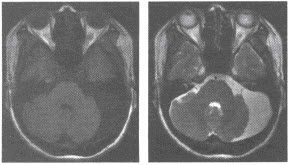

磁共振成像術的空間分辨室,也有待進一步提高。(一)顱腦與脊髓 MRI對腦腫瘤、腦炎性病變、腦白質(zhì)病變、腦梗塞、腦先天性異常等的診斷比CT更為敏感,可發(fā)現(xiàn)早期病變,定位也更加準確。

對顱底及腦干的病變因無偽影可顯示得更清楚。MRI可不用造影劑顯示腦血管,發(fā)現(xiàn)有無動脈瘤和動靜脈畸形。

MRI也叫核磁共振,MRI診斷被廣泛應用于臨床 MRI在神經(jīng)系統(tǒng)應用最早,也較成熟。

不僅可顯示灰質(zhì),白質(zhì),還可顯示一些神經(jīng)核,甚至可識別出腦神經(jīng),視神經(jīng)及傳導束。三維成像和流空效應,對病變定位不僅準確,還可了解病變與血管關系,給病變定性提供診斷依據(jù)。

應用MRI診斷顱內(nèi)原發(fā)性腫瘤和轉移瘤,顱內(nèi)感染,腦出血,腦梗塞,腦積水,腦血管畸形,脊髓和脊柱疾病具有特異性,優(yōu)于CT。對腦外傷有特異性,可檢出CT易遺漏的小血腫。